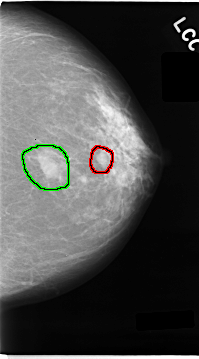

C_0024_1.LEFT_CC

FILE: C_0024_1.LEFT_CC.OVERLAY

TOTAL_ABNORMALITIES 2

ABNORMALITY 1

LESION_TYPE MASS SHAPE OVAL MARGINS CIRCUMSCRIBED

ASSESSMENT 3

SUBTLETY 5

PATHOLOGY BENIGN

TOTAL_OUTLINES 1

BOUNDARY

ABNORMALITY 2

LESION_TYPE MASS SHAPE N/A MARGINS ILL_DEFINED

ASSESSMENT 5

PATHOLOGY MALIGNANT